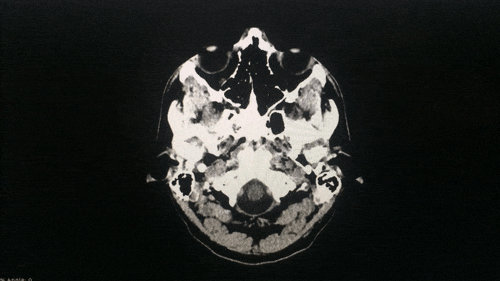

I had my brain scanned. Everything seems normal. I assume. Wanna see it?

And here’s the meat…

My insides are weird looking.